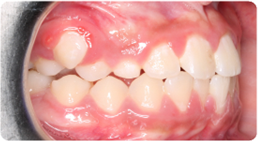

Each case shows the front view and an arch or side view, before and after BioLign Method-guided treatment.

High canine brought into the arch without extraction